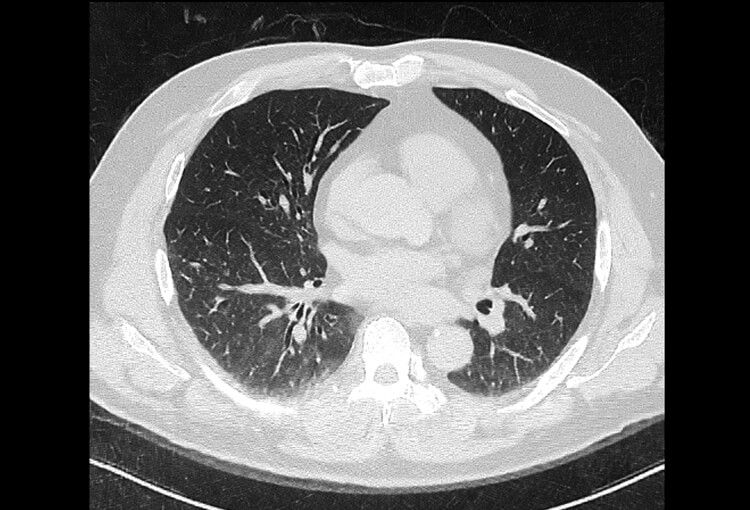

120 kV / 20 mAs / 1 mm

Before FBP (Noise 189) VS After ClariCT.AI (Noise 46) 76% Denoising